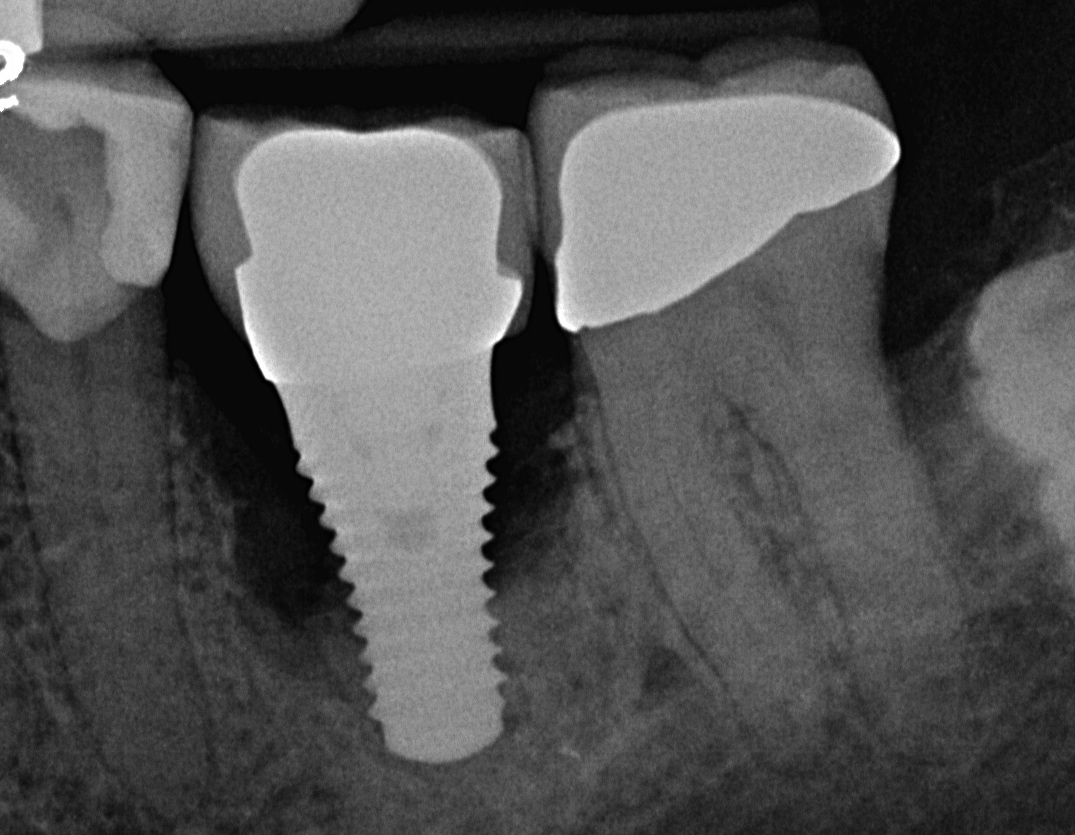

Fig 8. Radiograph taken 3 years after restoration of this mandibular right second molar implant demonstrating a peri-implant lesion.

Figure 8

Fig 9. Clinical view of this lesion shows the circumferential pattern to the bone loss.

Figure 9

Fig 11. Radiograph taken 1 year after regenerative therapy suggests favorable bone gain covering the entire roughened surface of the dental implant.

Figure 11